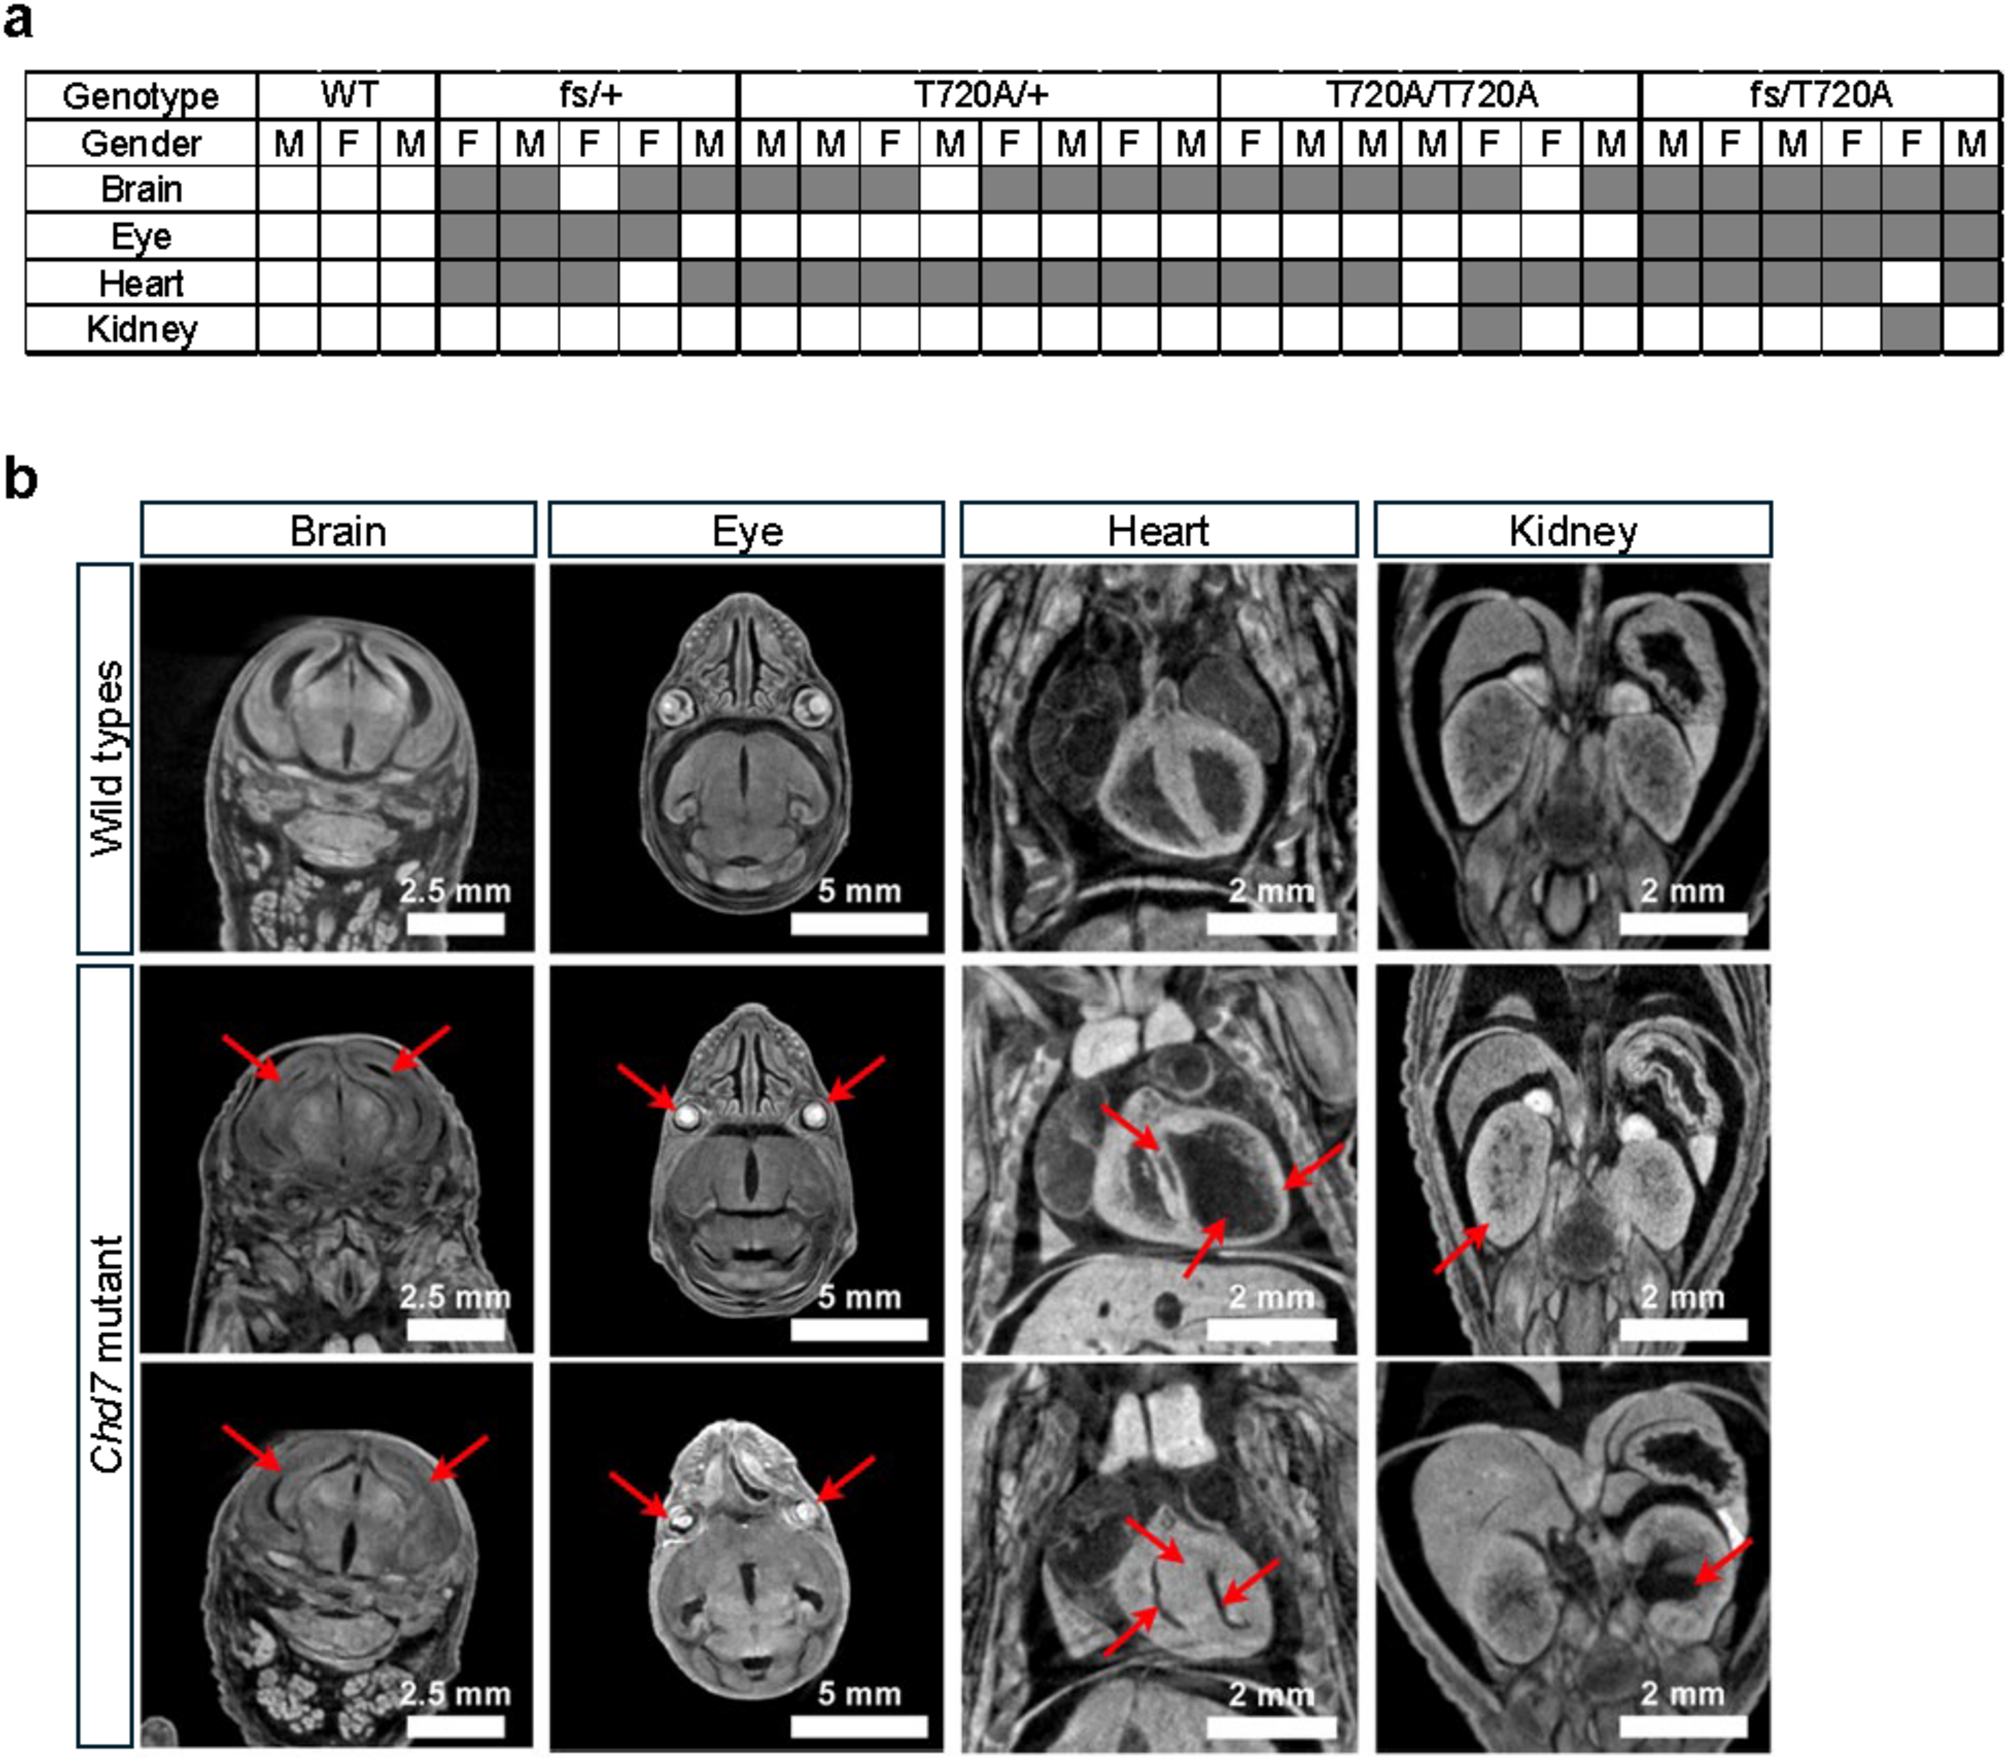

Gross morphology and 2D digital section phenotyping with iodine-contrasted micro-CT. (a) Table summarizing the occurrence of organ abnormalities in Chd7 mutants across different genotypes: WT (Chd7+/+), T720A/+ (Chd7), T720A/T720A (Chd7T720A/T720A), frameshift null fs/+ (Chd7fs/+), and compound heterozygous fs/T720A (Chd7fs/T720A). The analysis was performed on mouse embryos at embryonic day 18.5 (E18.5) using micro-CT. Shaded areas in the table indicate the presence of abnormalities in various organs including the brain, eye, heart, and kidney. (b) Representative micro-CT images showing the phenotypic abnormalities observed in Chd7 mutants. The abnormalities are indicated by red arrows and are organized by organ: Brain (reduced lateral ventricular size in Chd7T720A/+ and Chd7fs/T720A mutants), eye (microphthalmia observed in two Chd7fs/+ mutants, heart (enlarged ventricular chamber, thinning of the ventricular wall, and ventricular septal defect in Chd7fs/+ mutant; or reduced ventricular chamber and thickened ventricular wall in Chd7fs/T720A mutant), and kidney (enlarged kidney in Chd7T720A/T720A mutant; or hydronephrosis in Chd7fs/T720A mutant). Scale bars for reference are included in the images (2.5 mm, 5 mm, and 2 mm).